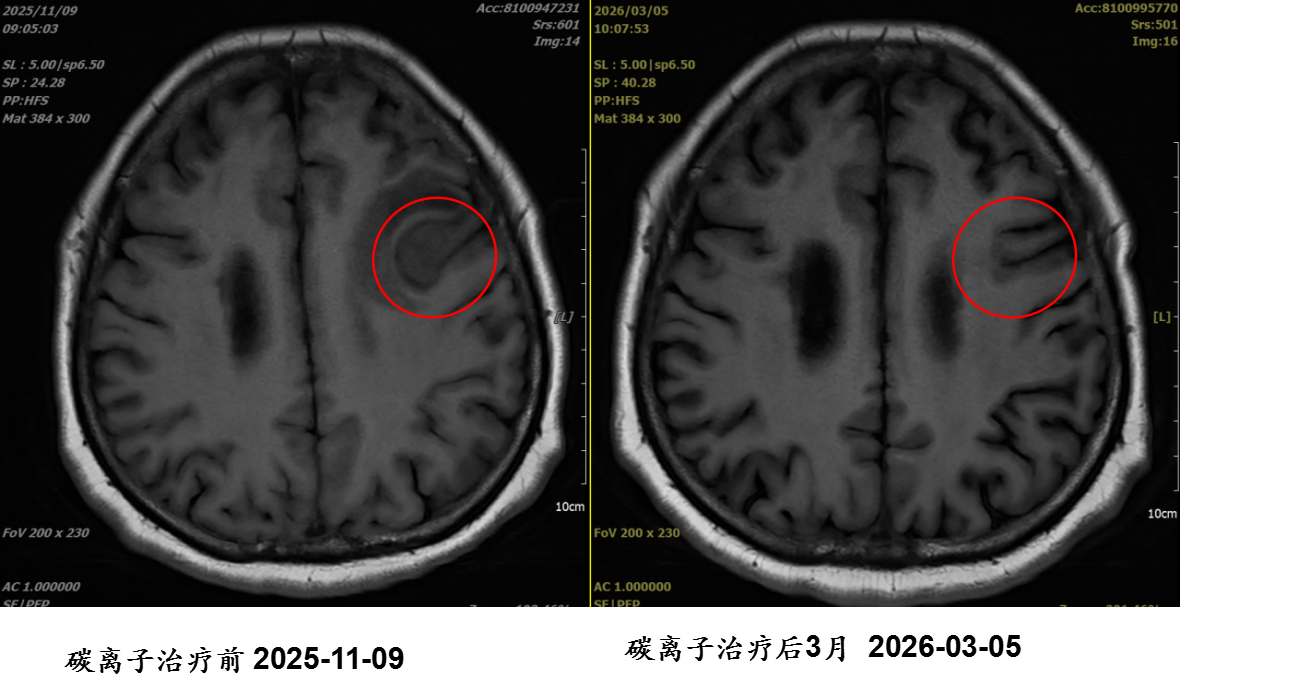

刘某某,女,56岁;主因“肺癌伴脑转移重(碳)离子治疗后3年余,左上肢无力1年余”入院; 诊断:1.右肺下叶恶性肿瘤(靶向、γ刀及碳离子治疗后) 腺癌 cT4N0M1c IVB期 2.脑继发恶性肿瘤; 重(碳)离子治疗:左侧额叶转移病灶重(碳)离子治疗。

病例提供医生:杨钰玲 科室:放疗中心一科(国际一部)